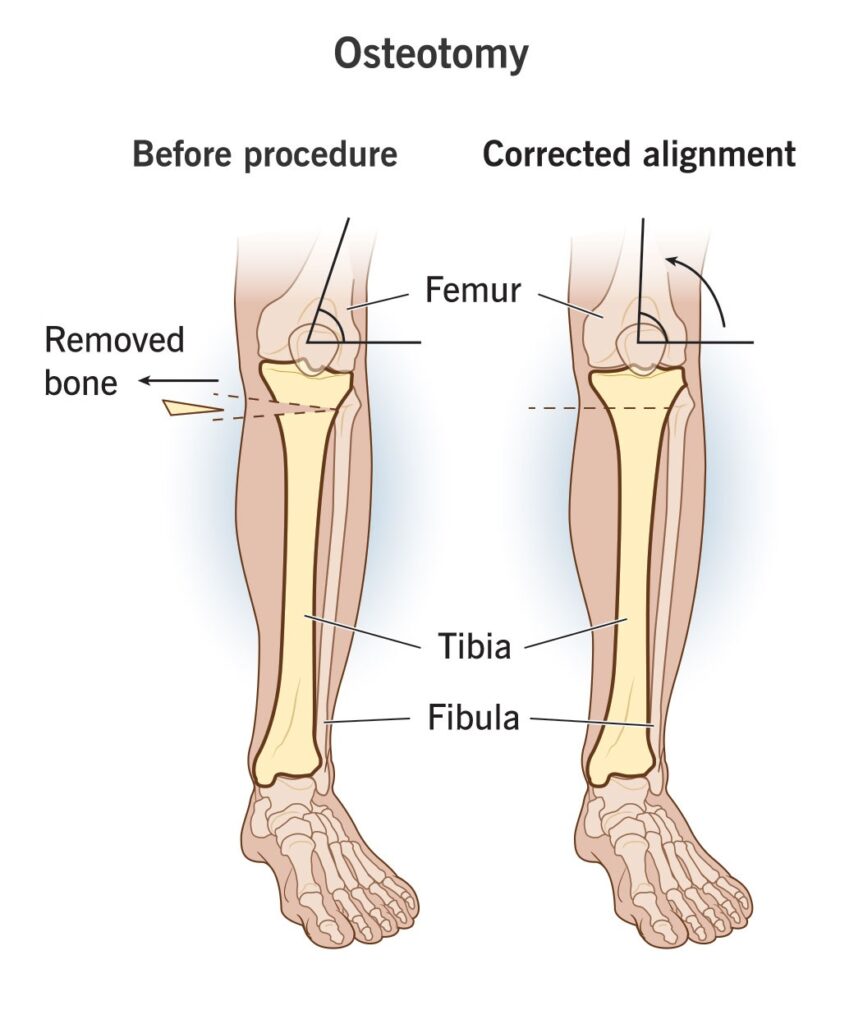

A knee osteotomy involves cutting and reshaping one of the bones that meet under your kneecap — your shinbone (tibia) or thigh bone (femur). It’s usually done to correct damage from arthritis. The surgery realigns your knee joint, shifting the weight and the pressure from your knee’s damaged side to the healthy side. Osteotomy of the knee is usually done in the early stages of osteoarthritis when the damage is only on one side of the knee joint.

The location of the knee osteotomy depends on where the damage is. For example, in a high tibial osteotomy, cartilage damage tends to be on the inside of your knee. The surgery involves removing either a wedge of bone from the outside of your knee or opening up a wedge of bone on the inside of your knee, creating a straighter leg and preventing the progression of arthritis.